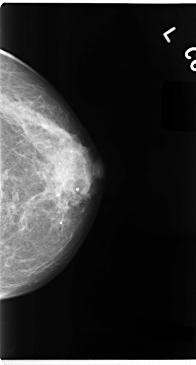

C_0077_1.LEFT_MLO

LEFT_MLO LINES 4752 PIXELS_PER_LINE 2464 BITS_PER_PIXEL 12 RESOLUTION 50 NON_OVERLAY